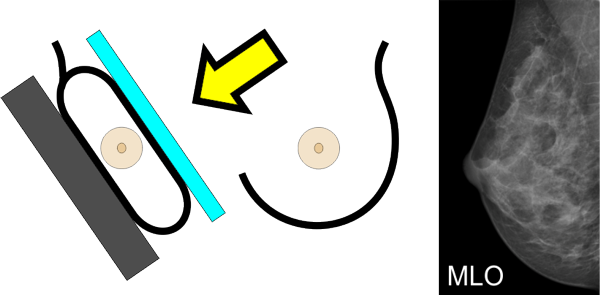

Von jeder Brust werden üblicherweise zwei Aufnahmen - jeweils von oben nach unten (cranio-caudale Aufnahme) und schräg von innen nach außen (medio-laterale oblique Aufnahme) - angefertigt. Die Brust wird dabei in eine Vorrichtung eingespannt und komprimiert:

können die Brustabschnitte in der Nähe der Achsel besser dargestellt werden.

Die Brust ist ein dreidimensionales Organ, die Aufnahmen sind hingegen flach. Um die sichtbaren Strukturen räumlich richtig einordnen zu können, sind daher zwei Aufnahmen in verschiedenen Ebenen notwendig.